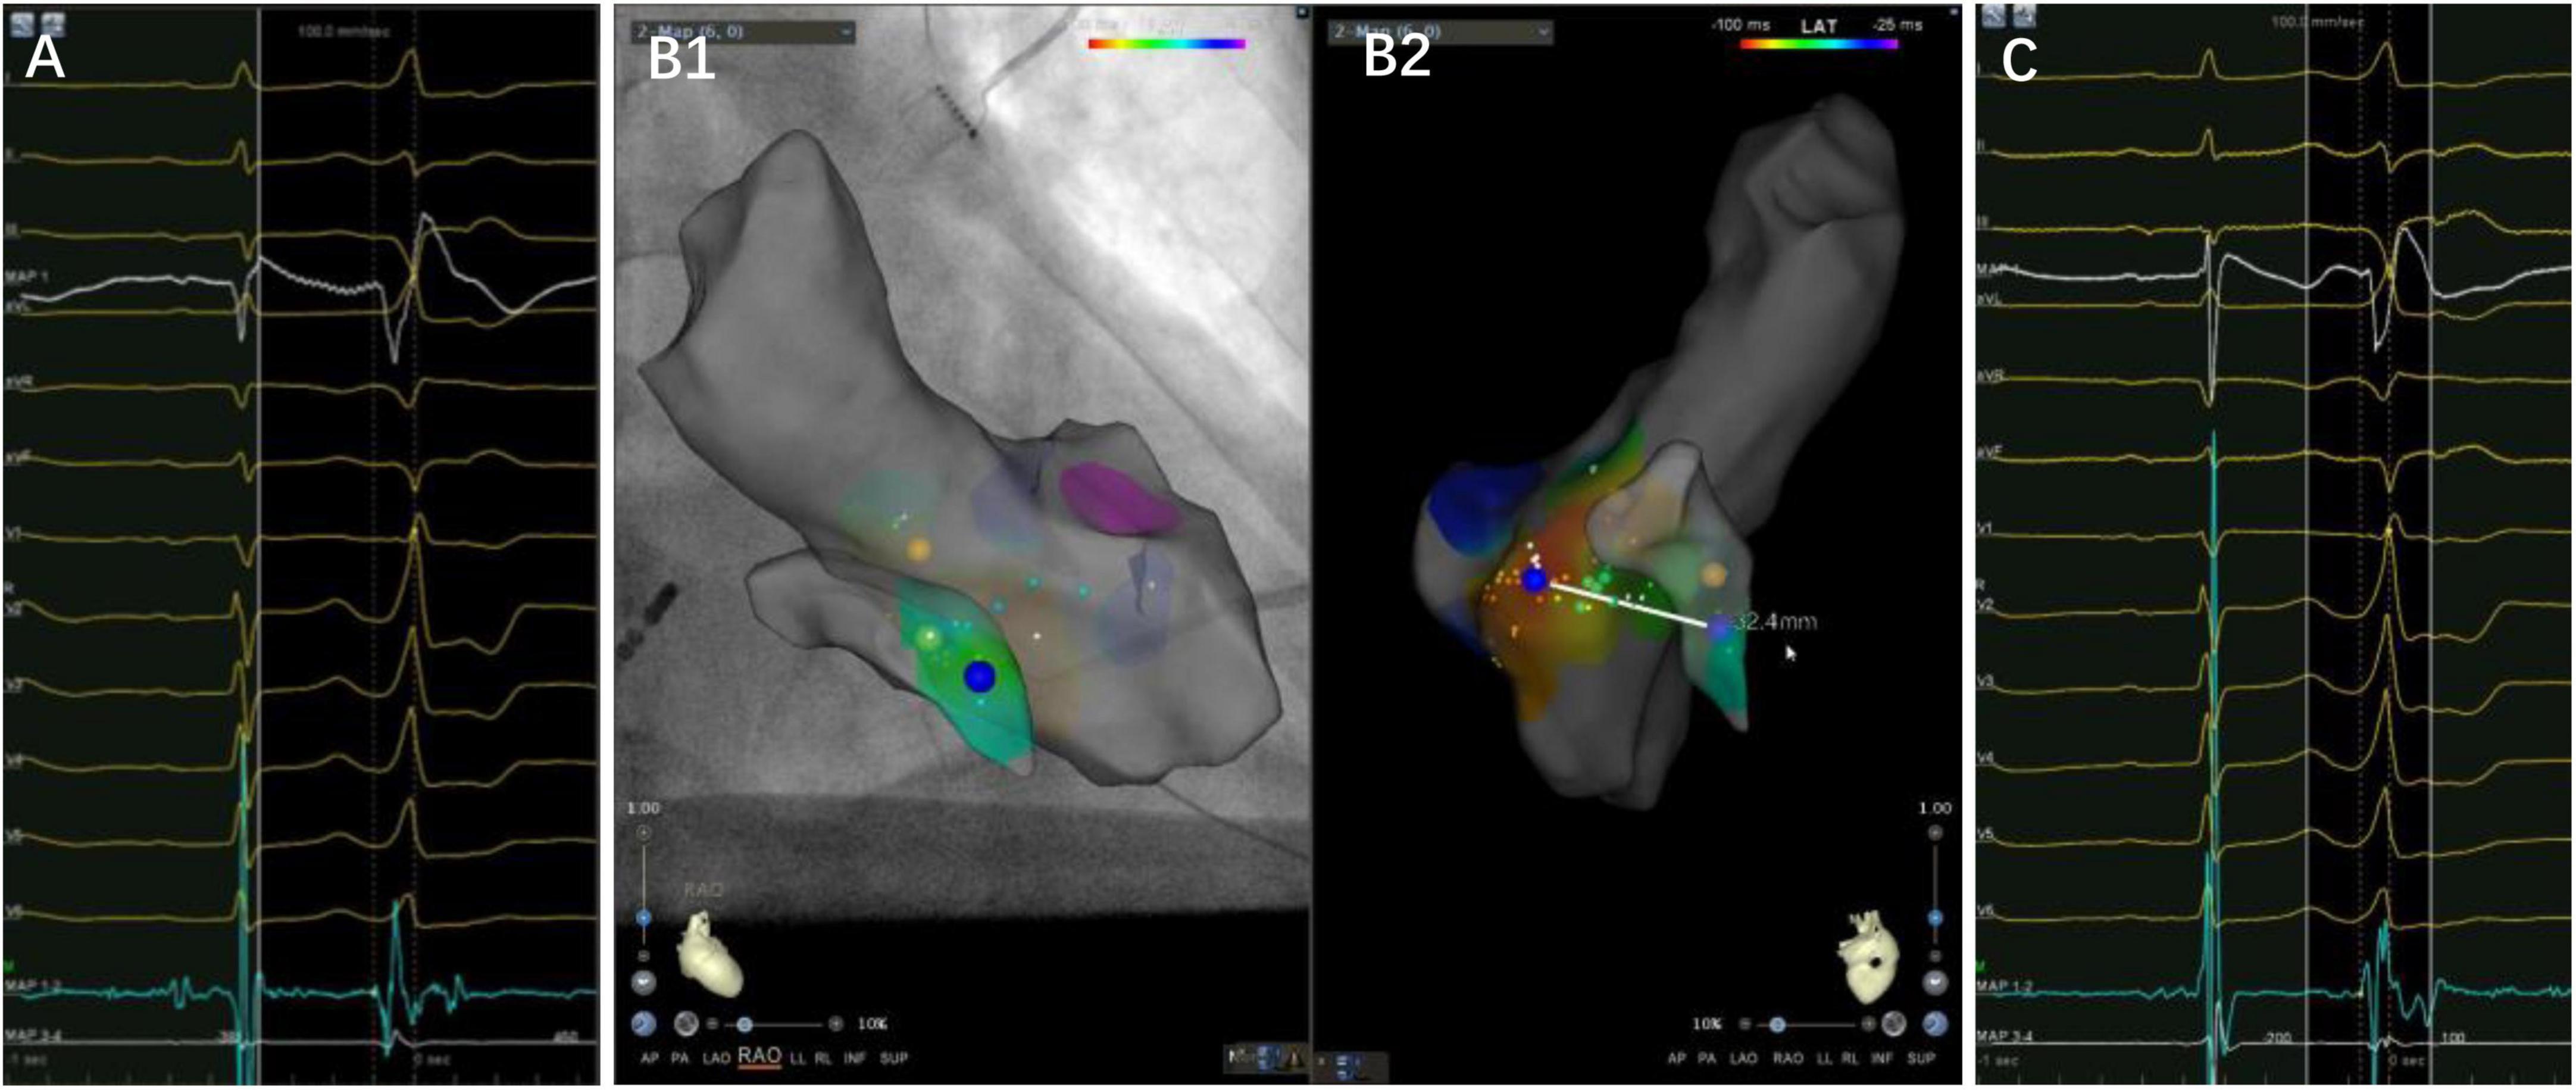

It was found that the VAs was eliminated using the under-valve approach in 36 patients (70.6%) after a 12 month follow up. Additionally, most of the patients demonstrated a small “a” potential at the target site, which suggested that these tachycardias could be classified into a septal group of VAs from the annulus (Figure 4). Nevertheless, basal septal area VAs has unique characteristics compared with arrhythmias from other parts of the annulus due to the following facts. First, sequential ablation from both sides of the septum was required in 47% of patients due to the exit shift, which reflects a deep or even intramural location of the VA origin in some cases (Figure 5). When catheter ablation on the tricuspid valve is unsuccessful, a catheter inversion technique of the under-valve approach should be attempted for mapping and adequate contact and stability of the ablation catheter (15). In some situation, an anatomical ablation approach is also a valuable option in basal septum from intramural foci. Meanwhile, the impairment of AV conduction should not be ignored during RFCA delivered to this region. In our study, first-degree atrial ventricular block in the acute period and complete atrial ventricular block 3 months after the procedure were observed in two and one patients, respectively. Second, due to the apical displacement of the septal tricuspid valve relative to Koch’s triangle, some VAs from the septal tricuspid annulus were successfully ablated from the low Koch’s triangle with no complications (14). Third, in those patients that need left-side ablation, a combined strategy employing a retrograde aortic approach and a transseptal approach should be considered. Consequently, based on the unique anatomical and electrophysiological characteristics, a systematic approach for VAs originating from the basal septal area is warranted.

Figure 4. A case of premature ventricular complex ablated from the left side of the basal septum. Panels (A–C) are the left side target potential, three-dimensional map and the earliest activation at the under-valve area of right side, respectively. The target electrogram precedes the QRS onset by 36 ms, while the earliest activation on the right side only 14 ms, with a distance of 32.4 mm between them. Notice a small “a” potential at the target electrogram.